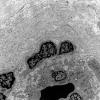

PERIPHERAL NEUROPATHY

11 VASCULITIS - VASCULOPATHY

2 Vasculopathy (4)